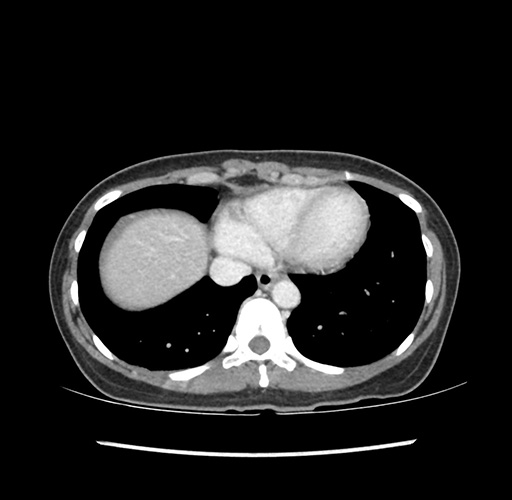

Imaging Analysis

Look through the patient's CT scan to identify any areas of concern for the necessary procedure.

Based on your CT findings, which issue(s) would give reason for "planned slowing down moment(s)" in this case?

Considering a standard left lateral sectionectomy procedure, what step(s) of the operation would you do differently in this case ?